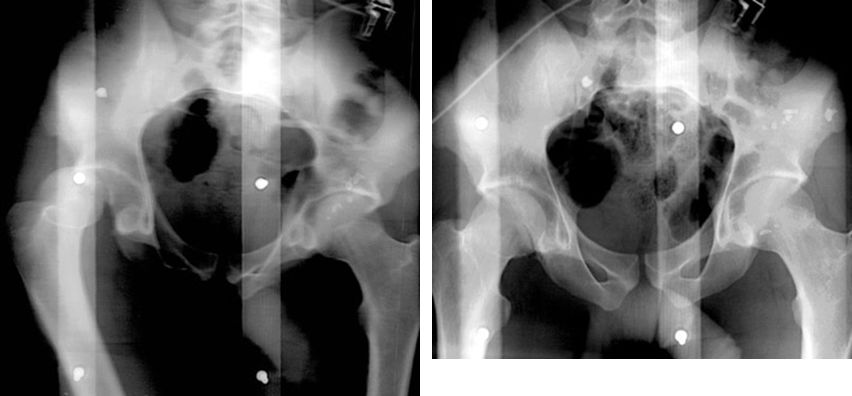

正常骨盆正位片

疼痛科怎么理疗疼痛科医生、康复理疗科医生、针刀针灸医生应掌握的常见骨科疾病X光片_https://www.jmylbn.com_新闻资讯_第47张

髋关节后脱位

疼痛科怎么理疗疼痛科医生、康复理疗科医生、针刀针灸医生应掌握的常见骨科疾病X光片_https://www.jmylbn.com_新闻资讯_第48张

髋关节前脱位

疼痛科怎么理疗疼痛科医生、康复理疗科医生、针刀针灸医生应掌握的常见骨科疾病X光片_https://www.jmylbn.com_新闻资讯_第49张